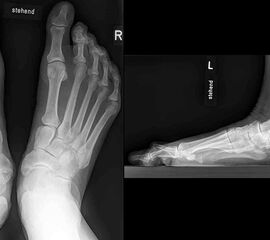

Konventionelles Röntgen

Stehende konventionelle Röntgenbilder eines Fußes mit Planovalgus Deformität Stadium II b dorsoplantar (dp) und seitlich. Auf der dp-Aufnahme zeigt sich die talo-calcaneare Divergenz, der gegenüber dem Kalkaneus nach anterior gleitende Talus und d

Stehende Aufnahmen des Fußes dorsoplantar (dp) und seitlich sowie des OSG anteroposterior (ap) sind die Grundlage der konventionellen Röntgendiagnostik (Abb. 5). Ergänzend werden gelegentlich die Rückfuβ-Alignement Aufnahme nach Saltzman 19 und Vergleichsaufnahmen der Gegenseite durchgeführt.

Der Talo-Metatarsale I Winkel bzw. die laterale talonaviculare Subluxation auf der stehenden dorsoplantaren Aufnahme des Fuβes dokumentieren das Ausmaβ des Vorfuβ abductus (Abb. 6 a,b). Ein dp Talo-Metatarsale I Winkel von > 10° (nach medial konvex) ist als pathologisch anzusehen. Mit der Bestimmung der talocalcanearen Divergenz (Abb. 6 c) erhält man ein Eindruck über das Ausmaβ des Rückfuβ valgus; eine leichte Divergenz bis ca. 12° gilt als physiologisch 20.

Auf der seitlichen, stehenden Aufnahme des Fußes wird ebenfalls der laterale Talo-Metatarsale I Winkel (Abb. 6 d) gemessen und so das kollabierte mediale Längsgewölbe dokumentiert. Auch hier gilt ein Talo-Metatarsale I Winkel von > 5° (nach plantar konvex) als pathologisch 21. Der Kollaps findet dabei meist im Talonaviculargelenk, seltener in der Naviculocuneiform-Gelenkreihe statt. Instabilität und Arthrose im 1. TMT sollten ausgeschlossen oder bei der Operationsplanung mit einbezogen werden. Weitere wichtige radiologische Messungen zur Beurteilung der Planovalgus-Statik und Progression der Deformität sind der laterale talo-calcaneare Winkel (Abb. 6 e) und der Abstand des Os cuneiforme-Unterrandes zum Untergrund (Abb. 6 f, Cuneiform height, 22. Eine anteriore Translation des Talus auf dem Kalkaneus findet man sowohl auf der ap, als auch auf der seitlichen Aufnahme des Fuβes mit Aufhebung der Cima-Linie.

Die stehende OSG ap -Aufnahme kann zunächst das fibulocalcaneare Impingement und im Endstadium laterale OSG Arthrose oder Valgus-Tilt des Talus zeigen.